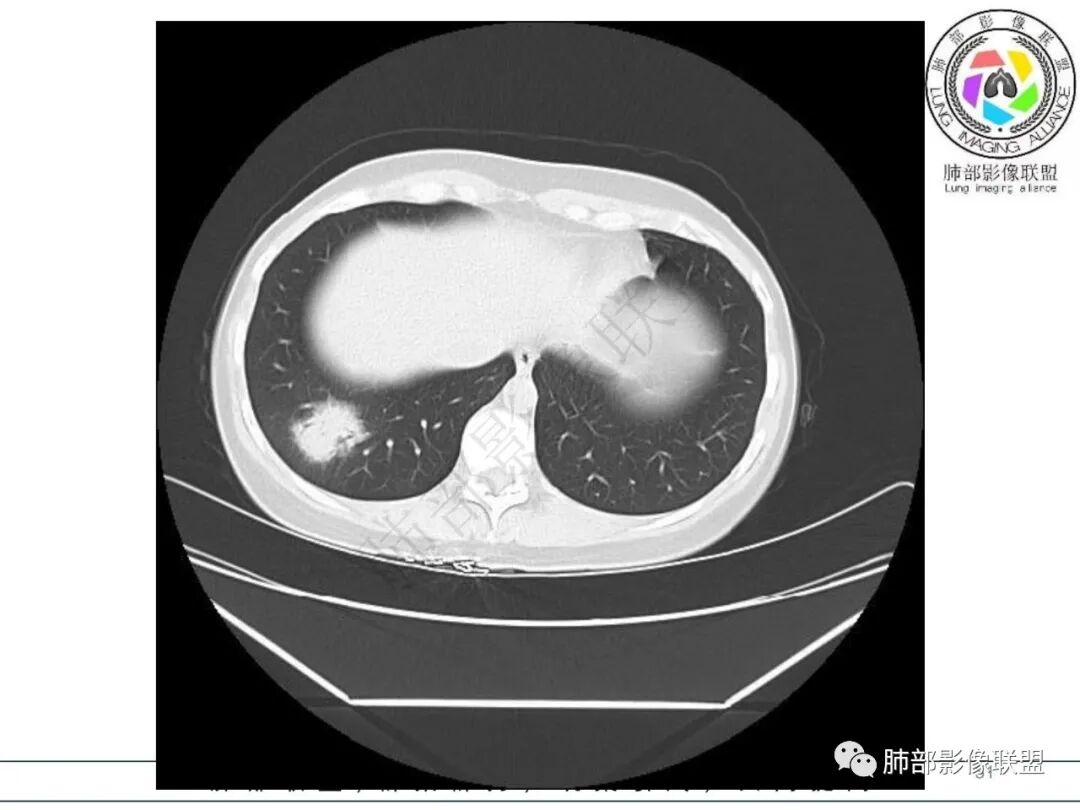

后、外基底段实变

周围GGO边界不清

内部支气管还算通畅

偏密实区支气管显示欠佳,密度稍低区支气管显示,密实区边缘稍膨隆

2.影像特征:右肺下叶局限性实变影伴晕征,边界不清,内部支气管尚通畅,实变区密实区边缘稍膨隆。符合炎性病灶特征。

3.综合分析:急性病程,炎性指标高,常见的是普通社区肺炎,如肺炎链球菌感染等。但本例患者临床表现较重,应先表现相对较轻,白细胞不高,须考虑非典型肺炎的可能性。本例隐球菌荚膜实验阴性,而军团菌临床症状一般较重,影像分布也更广泛、进展迅速,多器官损害更明显。因此考虑鹦鹉热衣原体可能性更大一些。其他如腺病毒等感染也是需要排除的。